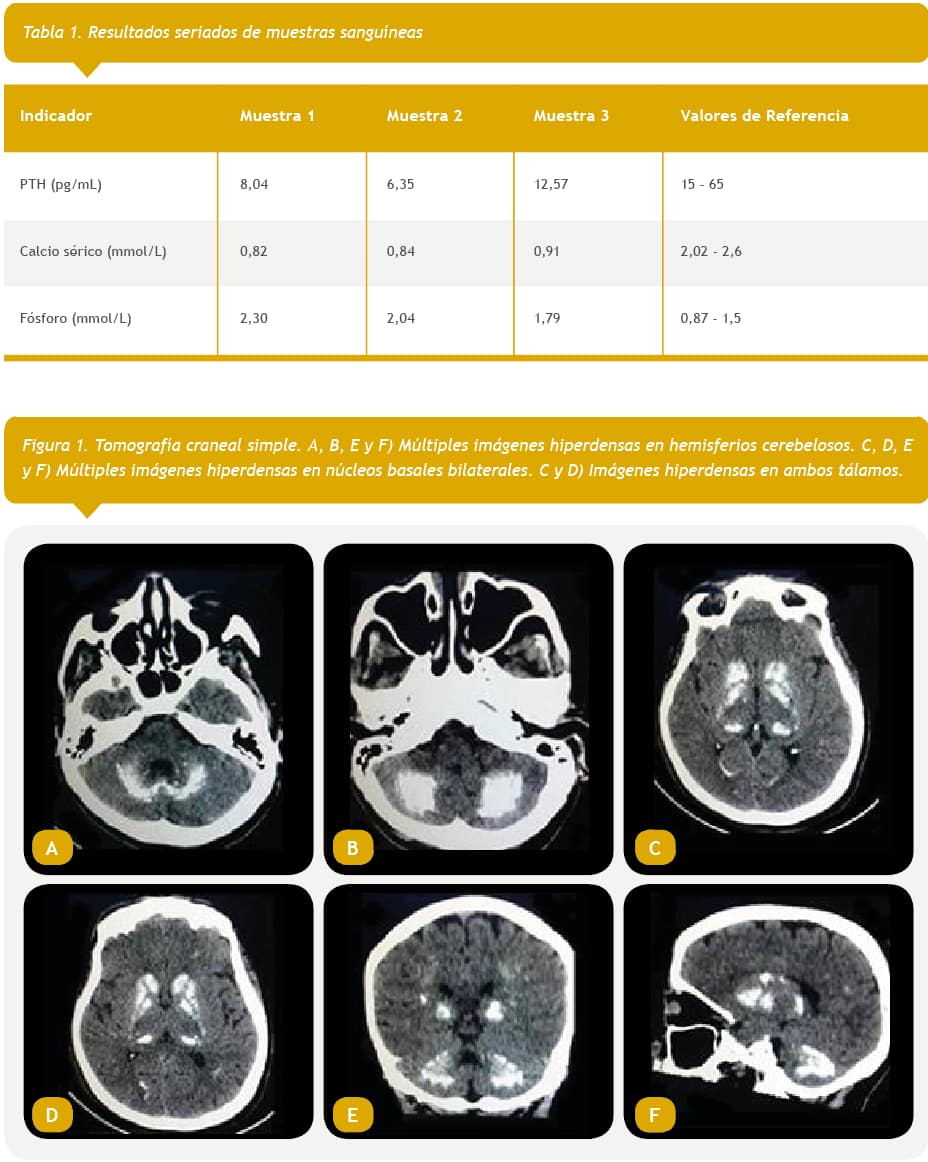

Durante su ingreso se realizaron estudios hormonales donde la hormona estimulante de la tiroides (TSH) y tiroxina (T4) resultaron normales (1,82 y 75,22, respectivamente). Sin embargo, las determinaciones de paratohormona (PTH) y calcio sérico fueron bajas durante toda la estadía hospitalaria, mientras que las de fósforo resultaron altas. El cortisol estuvo dentro del rango de la norma (510,3) (Tabla 1).

Se realizó una tomografía computarizada (TC) de cráneo en la cual fueron evidentes múltiples lesiones hiperdensas –con densidades óseas– en ambos hemisferios cerebelosos, núcleos basales bilaterales y ambos tálamos, que estaban en correspondencia con gruesas calcificaciones (Figs. 1 y 2).